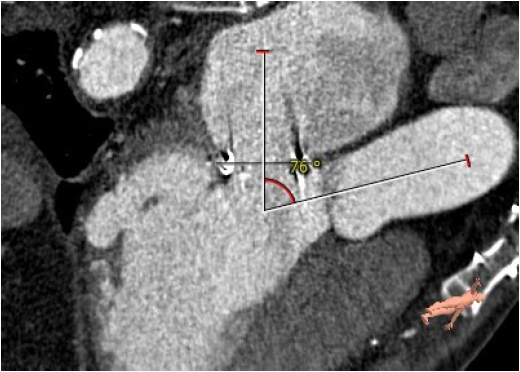

术前CT评估

主动脉与生物瓣轴夹角76°

左室与生物瓣轴夹角145°